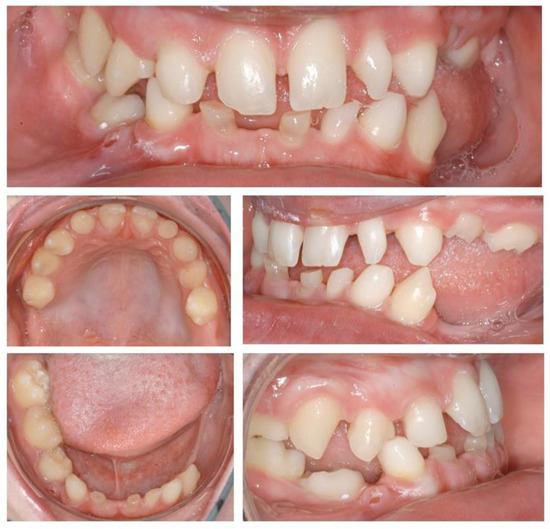

Figure 6.

Intraoral situation after orthodontic treatment and extraction of deciduous teeth.

At the time of implant planning, orthodontic treatment was already finalized. Dental implants were planned to replace missing teeth at sites 13, 23, 36, 45, 46. Despite adequate teeth alignment, wide interproximal spaces at sites 13 and 23 revealed the need of combined restorative and surgical treatments (Figure 6 and Figure 7). Thus, dental implantation in the upper jaws was associated with enlargement of lateral incisors and correction of form in the case of teeth 13, 23.